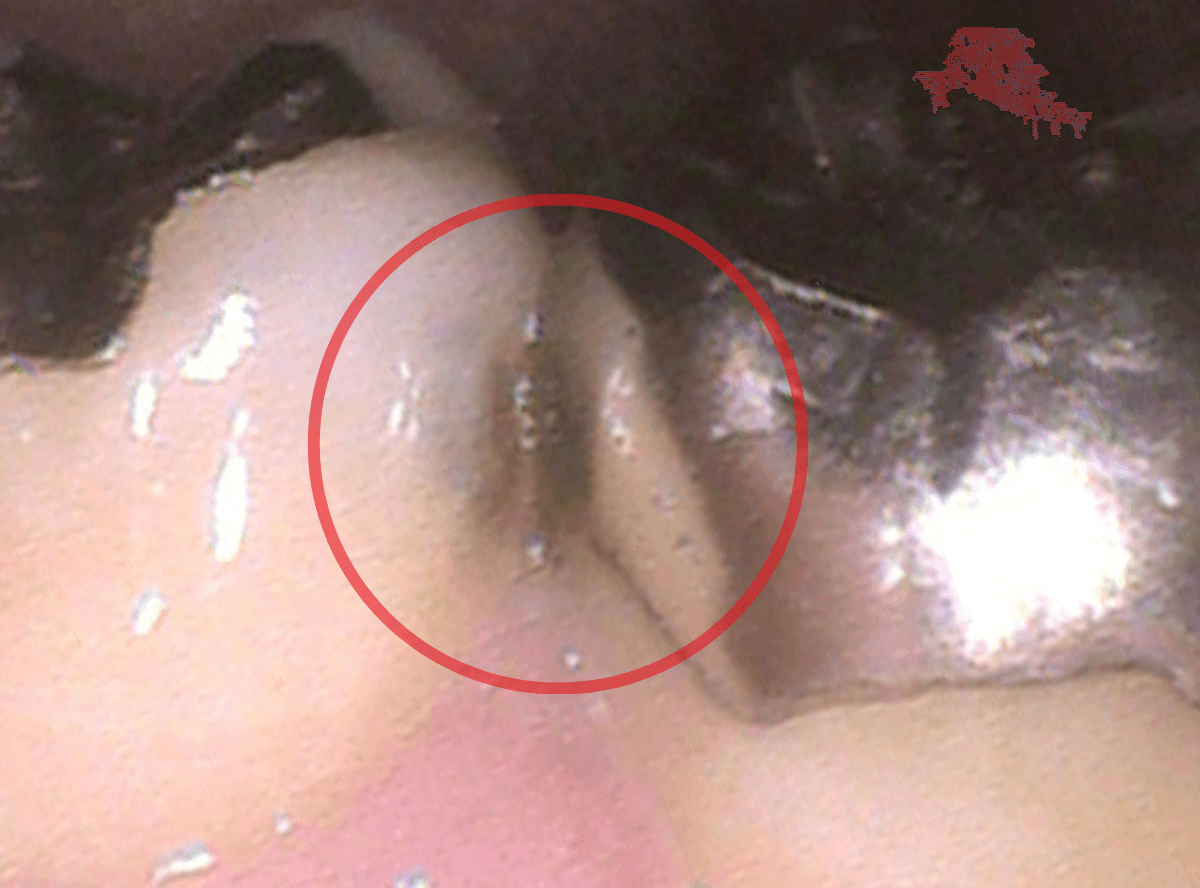

歯を裏側から見たところです。

幸い、見える部分に虫歯が

さし歯と歯肉の間に虫歯ができているのがわかります。

歯の奥まで虫歯が進んでいるのか、浅い虫歯ですんでいるのかは治療をしながら調べていく必要があります。